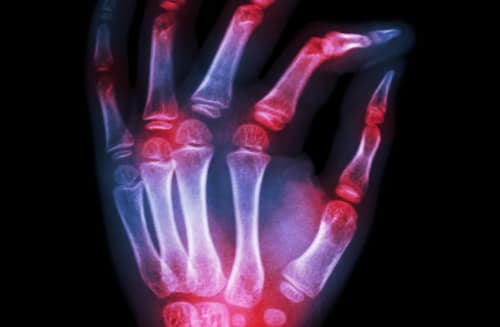

Lee sobre eficacia diagnóstica de anticuerpos antipéptidos citrulinados de segunda y tercera generaciones para la artritis reumatoide, Anticuerpos de Cadena Única de Alpaca, y mucho más